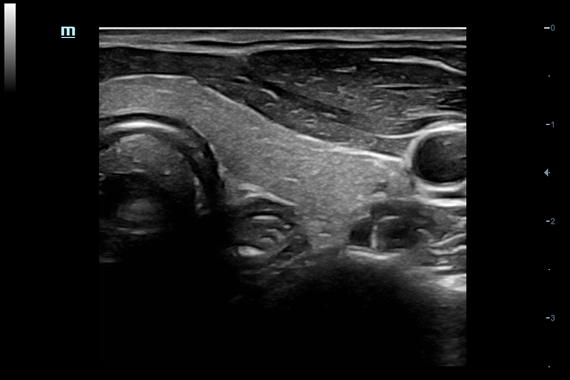

DC-60 EXP X-INSIGHT - это современный стационарный УЗИ-аппарат с функцией сенсорного управления и очищенной гармонической визуализацией, обеспечивающей лучшее контрастное разрешение и технологию 4D-визуализации. Он оснащен 21,5-дюймовым монитором, который может поворачиваться на 180 градусов, что удовлетворяет потребности врачей в качественной ультразвуковой диагностике.

• PSH™ - технология гармонической визуализации с фазовой инверсией.

• iBeam™ - режим многолучевого компаундинга.

• iClear™ - адаптивный режим шумоподавления.